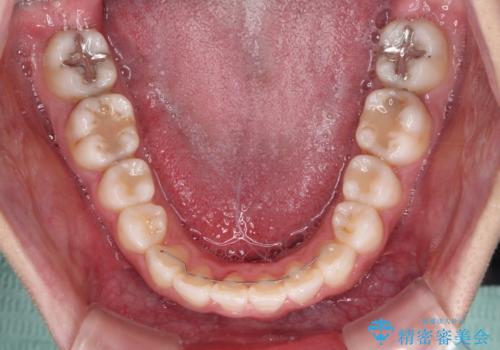

- ワイヤーではない矯正治療があると聞いたとのことで来院された患者様です。

長年前歯のデコボコを気にしていたもののワイヤー矯正に抵抗があり躊躇していたそうですが、インビザラインなら治療してみたいとのことで相談にいらっしゃいました。

インビザライン適用の歯列であったため、歯と歯の間を削るIPRを用いて改善することとしました。

お仕事柄、長時間のマウスピース装着が苦ではなかったので、歯列はすぐに整いましたが、ゆっくりとした交換頻度であったので、2年ほどの治療期間を要しました。